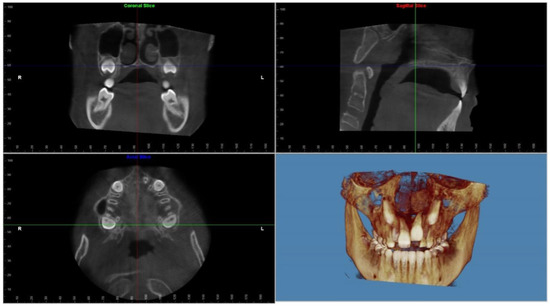

2. Materials and Methods